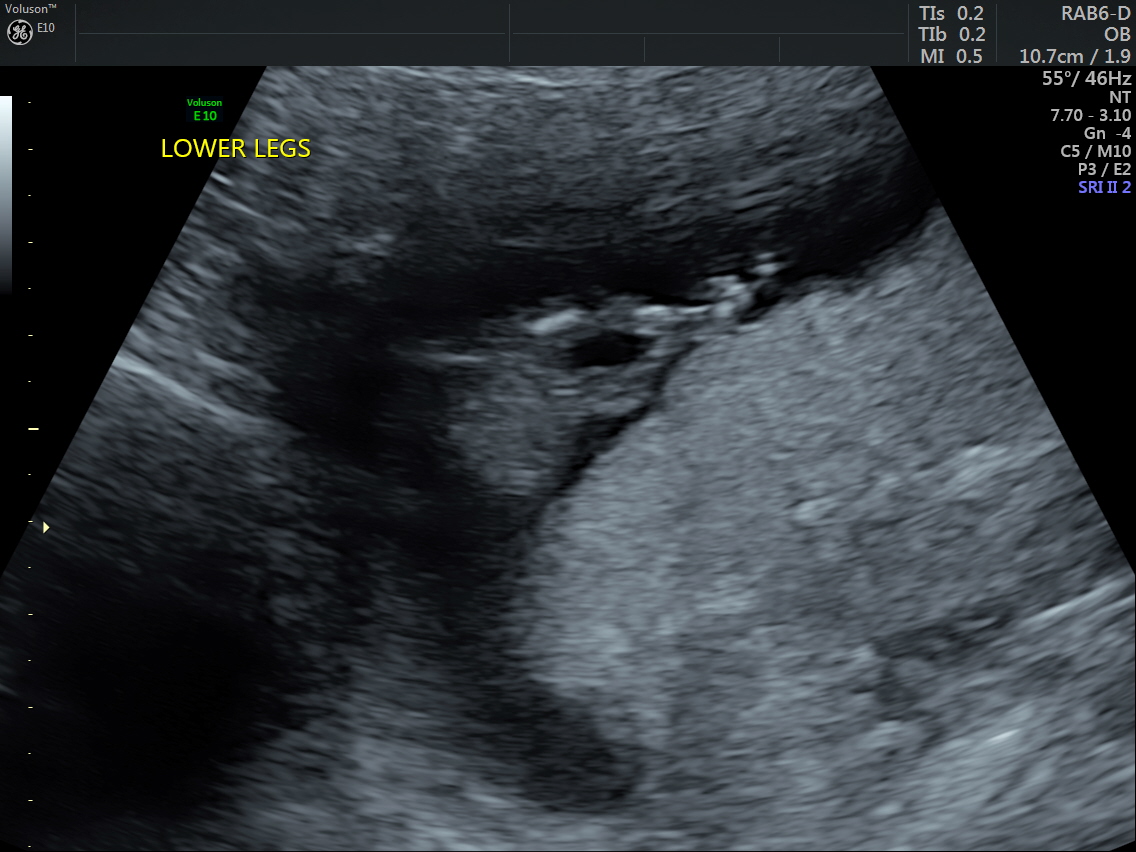

Does this picture show anything? Tech did guess boy, but she didn't know about nub theory and she went to look between the legs and took this pic saying it looked like boy bits.

I'm thinking boy. It looks like there is stacking. On the other hand, it's not classic party hat because it's a fork on top instead of a ball.

Hmm, that's a tricky one! My initial thought was blue, but then I scrutinised it a bit and thought it looks more pink....?